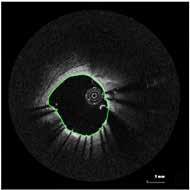

BIOMECHANICS OF ATHEROSCLEROSIS

COLLABORATION ON THREE NIH R01 STUDIES

1. Acquire Imaging Data

4. Identify Status

Acquire Undeployed Stent

6. Remove Stent from Lumen 5. Deform undeployed stent

3. Contour Lumen

7. Compute WSS